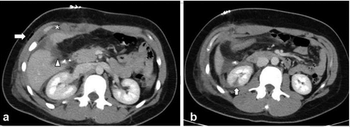

A team of international experts published seven recommendations for the use of chest imaging in the diagnosis and management of COVID-19-positive patients.

Images demonstrate high accuracy for identifying B-lines, thickened pleural lines, and pulmonary consolidation features.